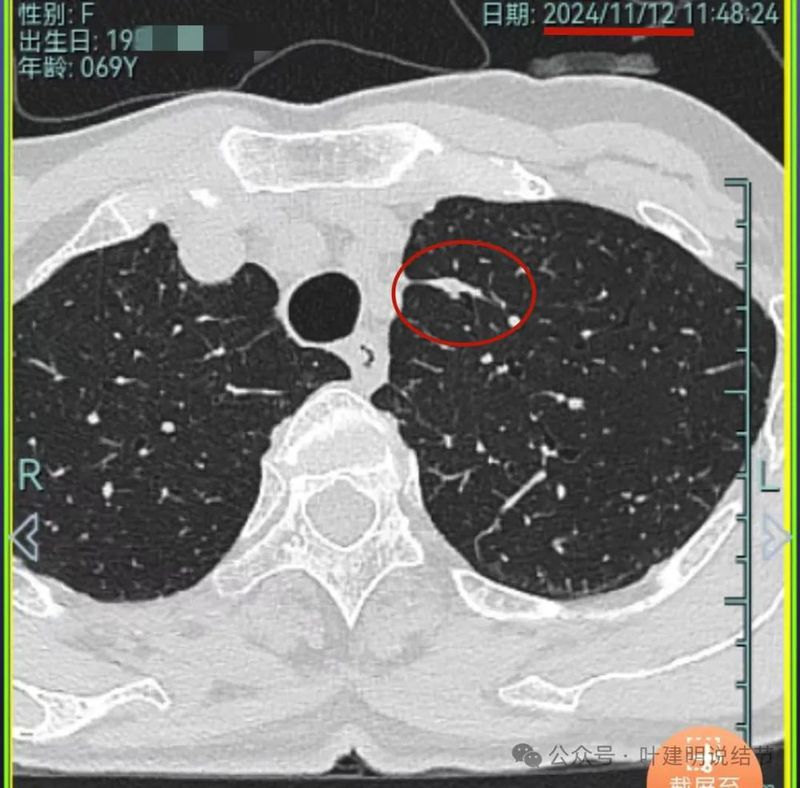

再看2024年11月复查的情况:

病灶1仍磨玻璃稍高密度,有血管进入,大小无显著进展,但密度从开始到现在是有所进展的。

我想我们这样也来考虑问题:1、左侧已经手术的确诊是肿瘤性质,左上已经消融的也是随访持续存在的磨玻璃密度结节,虽然没有病理依据,仍然要考虑广义上来讲的肿瘤范畴,看了以前的片子,从2019年到2023年并没有显著的进展,大概是肺泡上皮不典型增生可能性大。右侧的也有磨玻璃结节与混合磨玻璃结节考虑是肿瘤范畴的。所以总体上两肺多原发早期以磨玻璃为表现的肺癌,整体风险都不大。2019年切除的左肺下叶病灶也是纯磨玻璃密度,其实如果继续随访或者只做楔形切除也并没有什么关系。这说明体质本身或者致病的因素,就是容易长磨玻璃肺癌的,即便把目前发现的都解决,后续仍可能再有新的。原因不明,致病因素仍在。2、右肺上叶红色之处从2019年开始,是逐渐进展的,当然即便是现在,也不是说危险就已经很大,考虑仍然是原位癌或者微浸润性腺癌可能性大;中叶蓝色这处乍一看像至少是微浸润,但前后对比以后发现从2019年到现在,几乎没有显著进展,这样的话慢性炎伴肺泡上皮增生或者伴纤维增生也是有可能的,至少风险并不能认为大;右肺下叶黄色这一处,使纯磨玻璃密度,整体轮廓与边界清楚,考虑是肿瘤范畴的,不典型增生可能性较大,也有可能原位癌,随访稍有进展,风险仍然不大;中叶绿色这处是慢性炎伴钙化的,靠近叶裂的地方也像慢性炎,但此处随访有所进展。不过因为有卫星灶,整体显得比较散,所以虽然恶性可能性较大,但也不能完全除外炎性的可能性。当然如果此灶确实恶性,那风险则相对较其他进展缓慢的要高一些。从目前右侧所在的这些病灶来讲,真正有一定的风险而且最为确切的是红色这处,而且应该也没有到浸润性腺癌或者说不处理会要转移很危险这种程度。3、明确了多原发早期肺癌没有办法预防与控制,也明白了目前已经存在的较明显的这些病灶总体风险的高低。我们再来考虑需不需要近期干预处理。左侧既手术过又消融过,右侧的多发病灶目前又还没有到危险很高的程度,又没有办法预防后续再有新的病灶。我个人偏保守,我觉得仍然可以半年复查随访,如果最具风险的病灶有进展并且不处理可能导致不良后果,到这样的程度再来考虑综合如何处理干预便可。4、假如右侧我们予以处理,上叶红色的以及中叶蓝色的都可以楔切,但绿色考虑良性的再进展或以后像恶性时怎么办?而若中叶切除加上叶楔切,在左侧已经手术过的情况下肺功能影响相对也不小,何况右下比较中间的位置还有桔色这处呢。当然右下这处得考虑消融。所以,我的想法还是能熬再熬下,待其他监测有变化再通盘考虑。意见供参考!